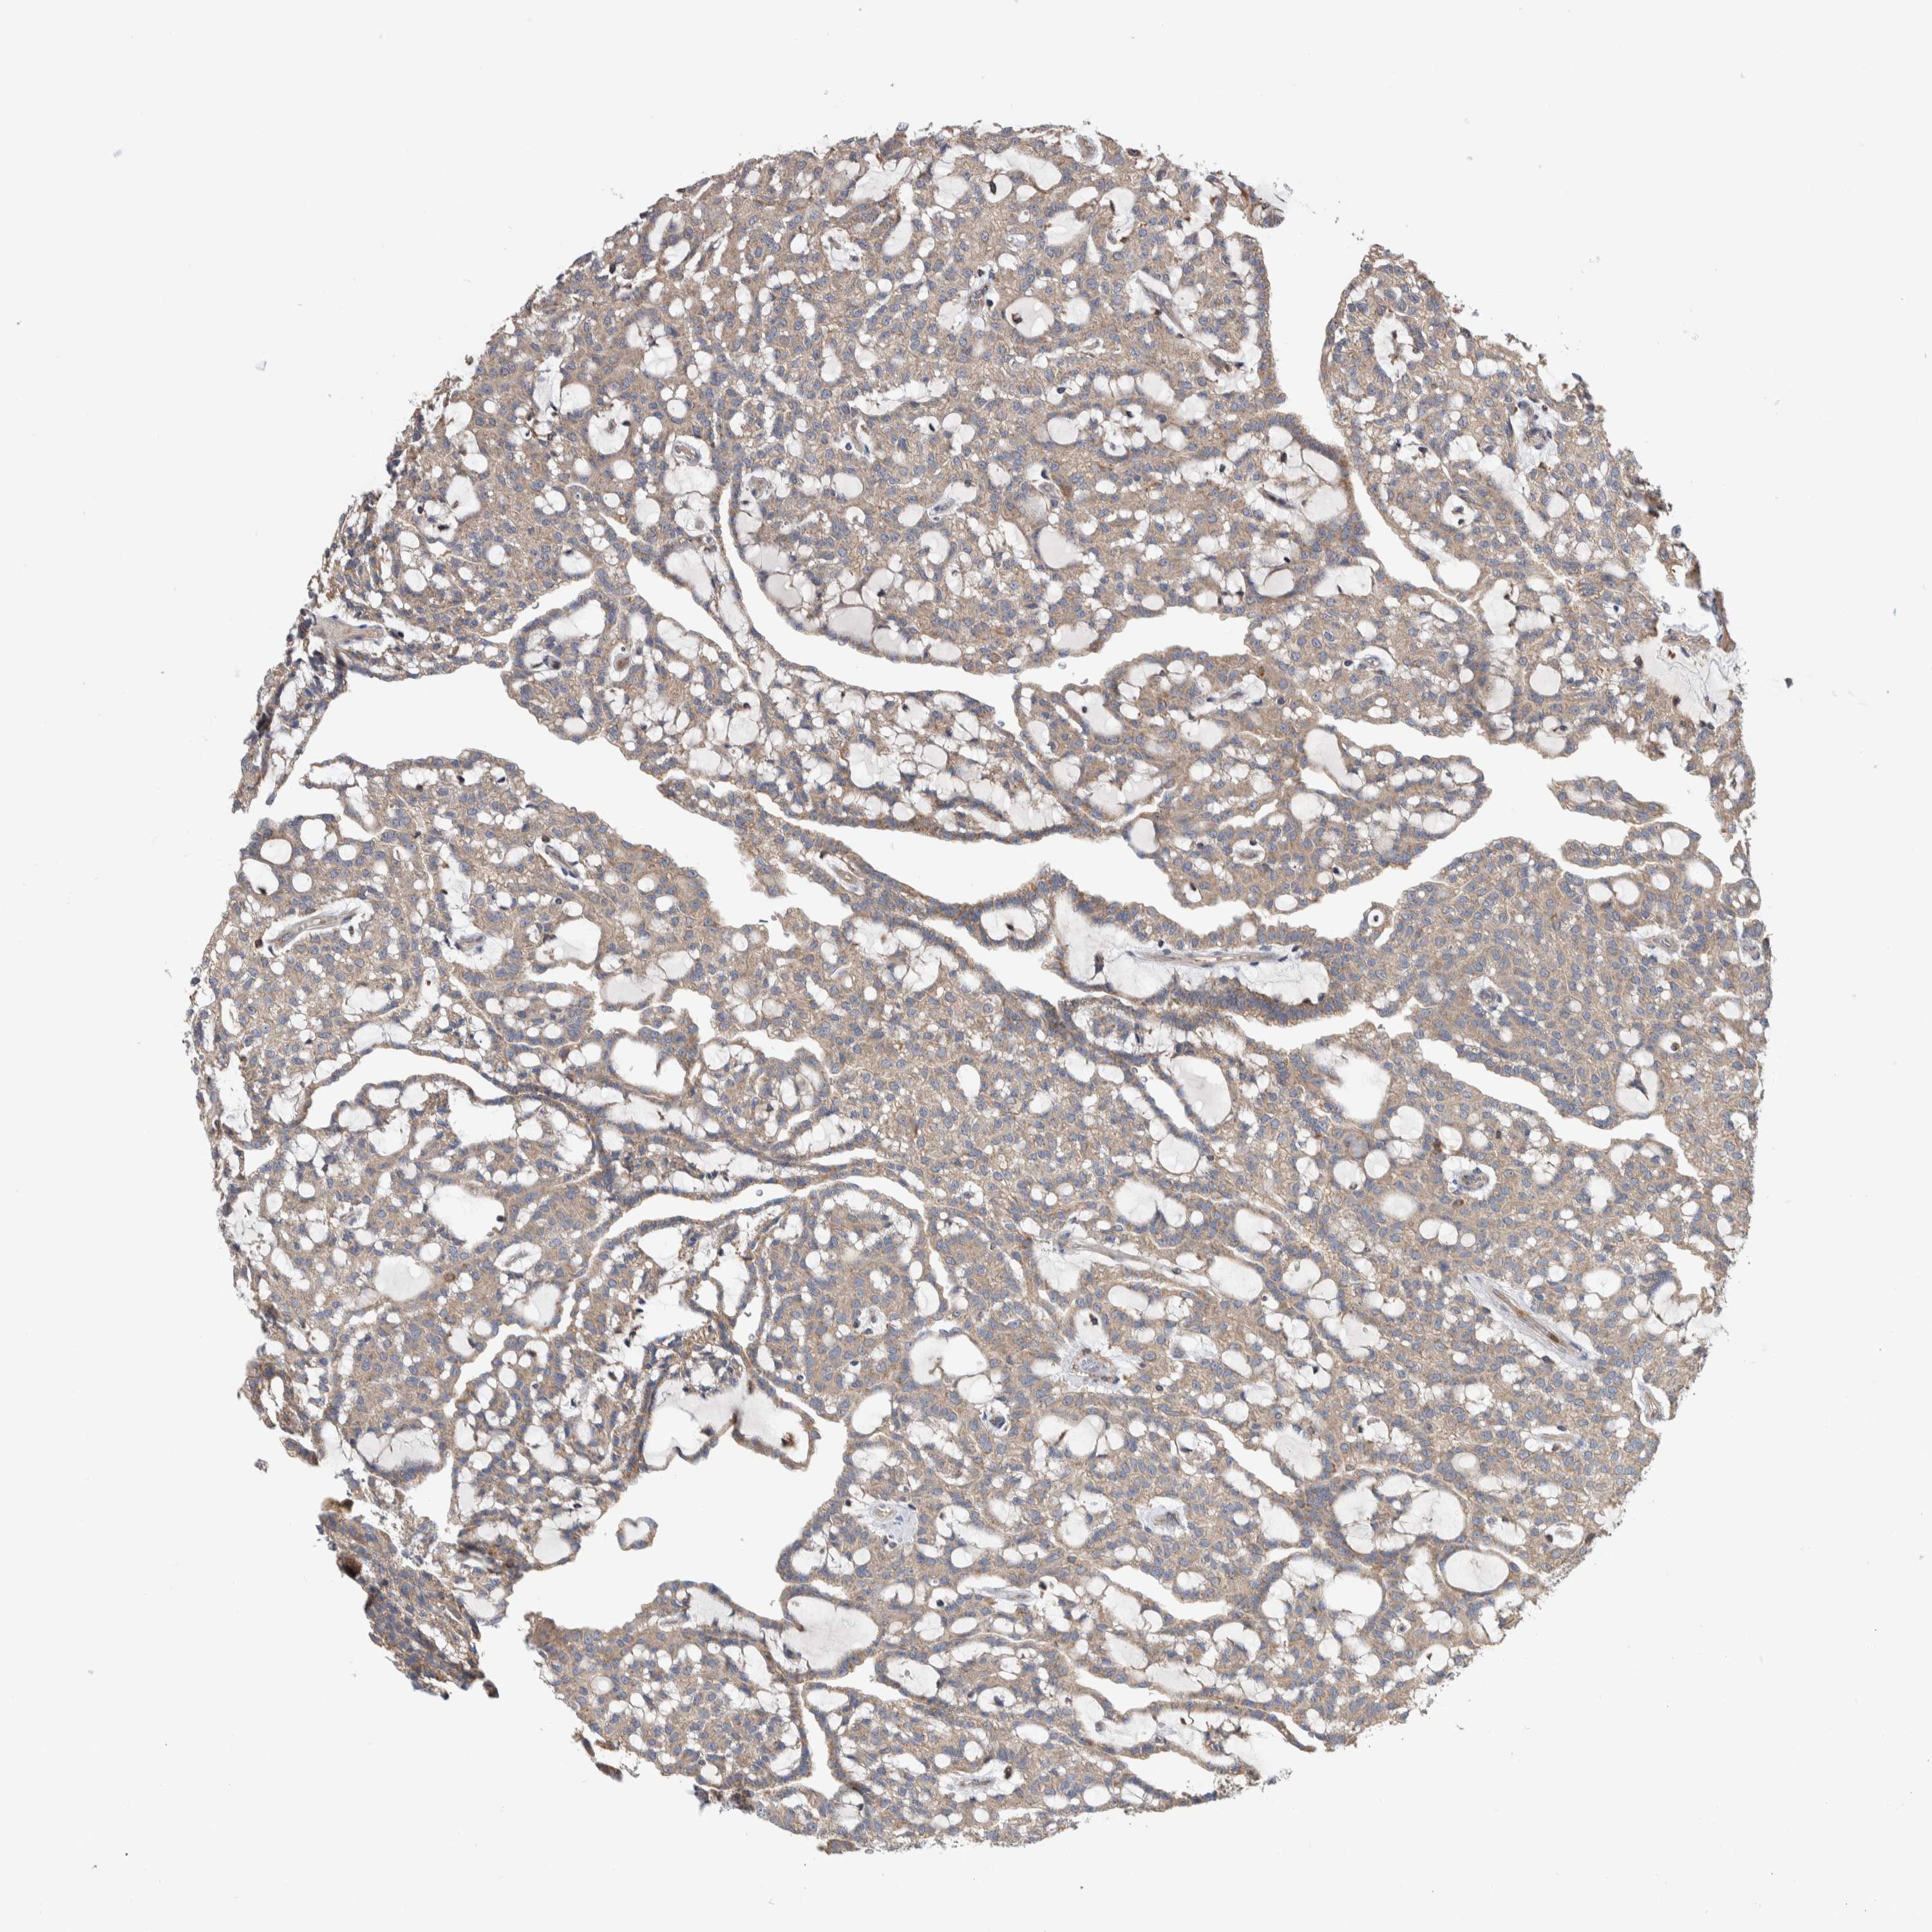

CANCER RENAL CANCER Show tissue menu

KICH TCGA KIRC TCGA KIRC VALIDATION KIRP TCGA PROTEIN RCC CPTAC PROTEIN EXPRESSION